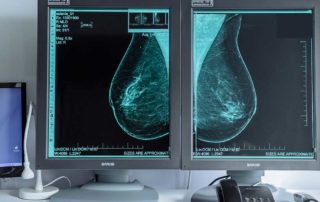

3D MAMOGRAFIJA: TOMOSINTEZA+SINTETISANI 2D MAMOGRAFSKI SNIMCI

Tomosinteza je savremena rengdenska metoda pregleda dojki kojom se umesto mamografskog snimka dojki dobije serija tankih izuzetno kvaltitenih snimaka dojke širine oko 1mm za svega nekoliko sekundi.Od sada vam je ova vrsta pregleda dostupna u Poliklinici Consilium Centar za dijagnostiku [...]